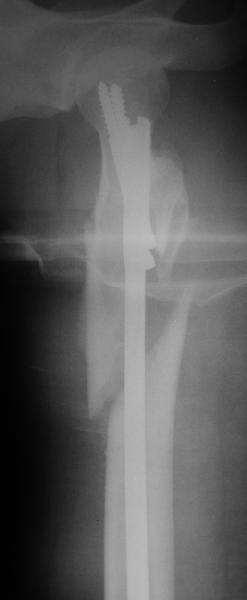

Оперировали вчера. Не сказать, что все прошло гладко - вертельная область была расколота и в сагиттальной, и во фронтальной плоскости, гвоздь попал в перелом и сместился кзади, что заметили уже после введения винтов, пришлось все извлечь и переставить. Снимки в приложении. Буду признателен за комментарии.

Если честно, мне не нравится стояние отломков

проксимального отдела. На мой взгляд причина в недостаточной осевой тракции сегмента перед этапом дистального блокирования. Если это действительно так, я бы попробовалудалить дистальные блокирующие винты, дать осевую тракцию(дистрактор, ортопедический стол, др.) и повторное дистальное

блокирование.

уважаемый А.Ч.! Не уверен, что отломки сопоставлены хорошо. Особенно плохо лбстоят дела с малым вертелом. Клинический исход по-видимому будет неудовлетворительным.